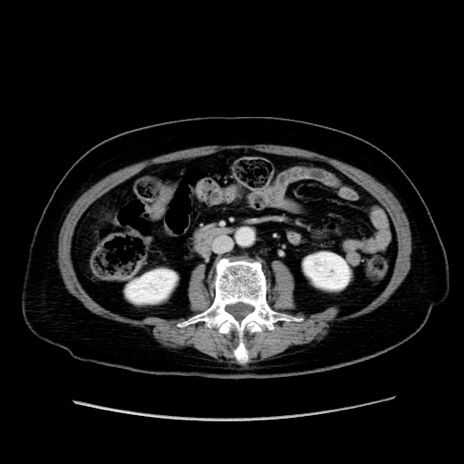

症例19(横断像)

【症例】80歳代女性

【主訴】下腹部痛

【現病歴】約8時間前より下腹部痛の出現あり、救急外来受診。

【既往歴】両側付属器切除

【身体所見】意識清明、下腹部正中に手術痕あり、その部位に一致して圧痛と反跳痛あり。腸蠕動音は亢進。

【データ】WBC 9300、CRP 0.15